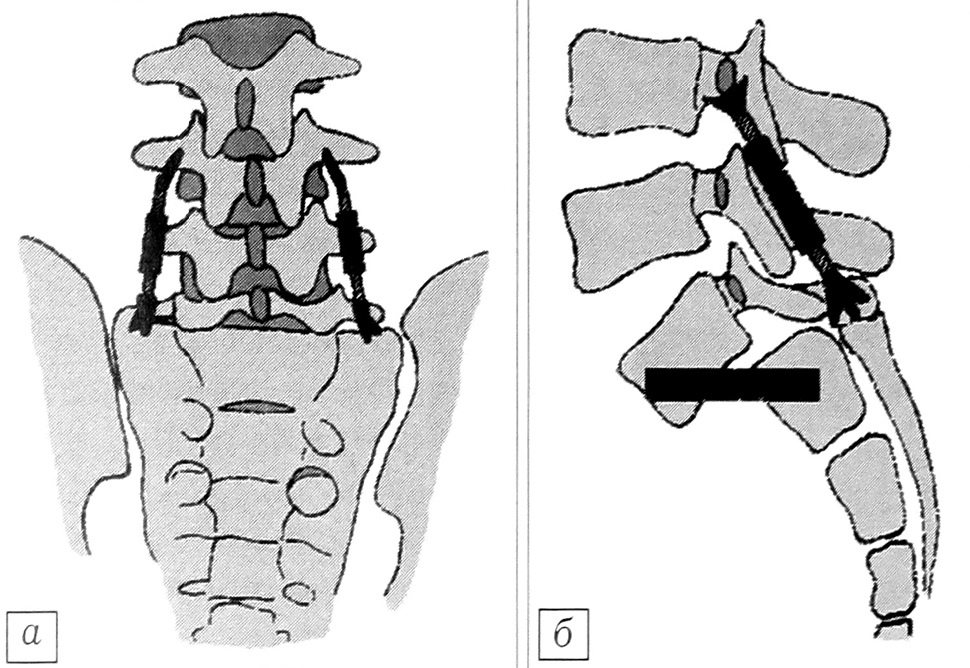

При небольшой степени смещения (до III) мы сочетали металлофиксацию с задним и заднебоковым спондилодезом аутои аллотрансплантатами. Больным с III—IV степенью спондилолистеза и спондилоптозом проводили двухэтапное хирургическое лечение. Первым этапом осуществляли дорсальную фиксацию дистракторами Казьмина (7 больных) или фиксацию транспедикулярным инструментарием (16). В обоих случаях фиксация дополнялась задним спондилодезом. В среднем через 2~3 мес выполняли второй этап оперативного лечения — передний межтеловой спондилодез аллои аутотрансплантатами из внебрюшинного доступа (рис. 1).

Рис. 1. Схема двухэтапной операции: фиксация пояснично-крестцового отдела двумя дистракторами Казьмина (а) и передний спондилодез L5-S1 кортикальным трансплантатом (б).